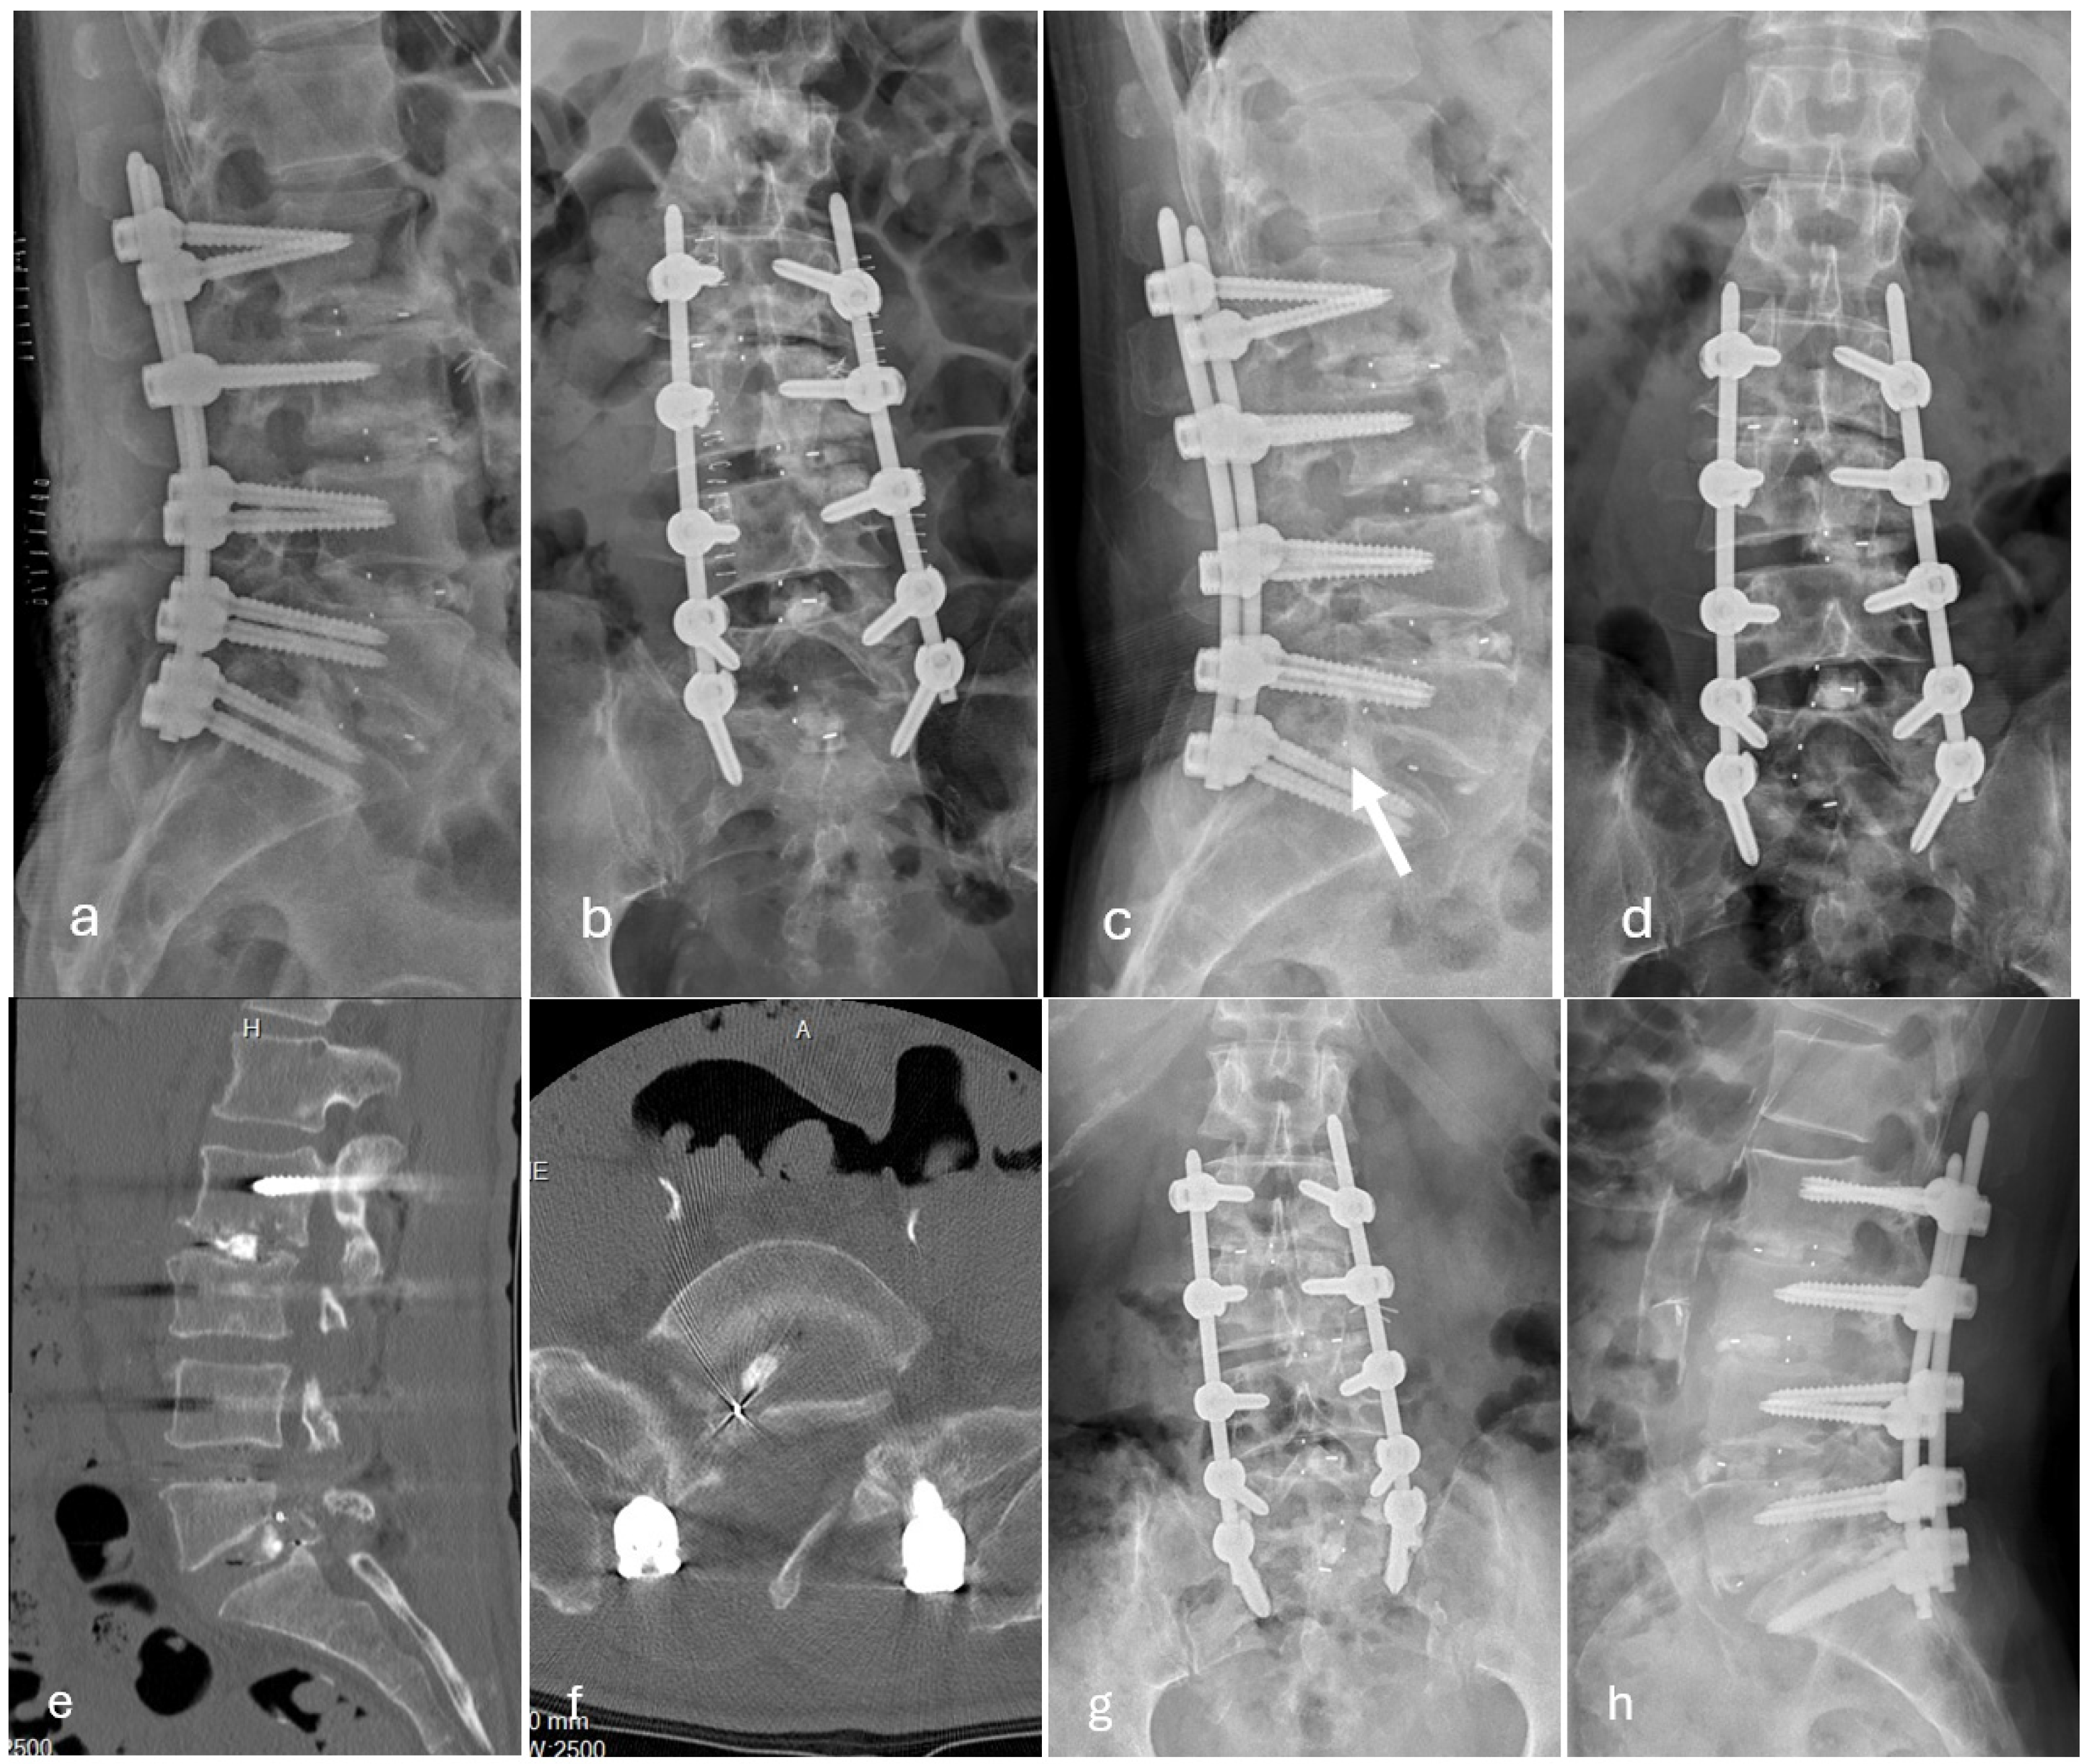

Among the 27 patients who developed posterior cage migration, 7 patients required revision surgery owing to symptomatic neurological deterioration (Figure 1), whereas 20 patients were managed conservatively without surgical intervention (Figure 2).

Figure 1. Representative imaging following minimally invasive transforaminal lumbar interbody fusion at L2/3, L3/4, L4/L5, and L5/S1. (a,b) Postoperative radiographs obtained on postoperative day 3 demonstrate appropriate interbody cage positioning at all operated levels. (c,d) Follow-up radiographs at 2 months after surgery show posterior migration of the interbody cage at the L5/S1 level (arrow). (e,f) Computed tomography images reveal posterior protrusion of the interbody cage into the spinal canal. (g,h) Post-revision radiographs demonstrate successful implantation of a new interbody cage via a contralateral left-sided approach.